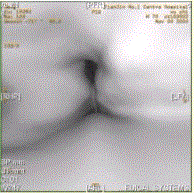

问题 患者男,60岁,声音嘶哑半年,CT表现如下图。 有关喉癌,正确的表述是

选项 A.喉癌以鳞癌多见 B.声门上区淋巴结转移最常见,声门下区次之 C.声门区喉癌好发于声带后1/3与中1/3的交界处 D.喉癌诊断中最重要的内容之一为评价前联合有无受累 E.CT仿真内镜可清晰显示声门区病变 F.喉癌以腺癌多见

答案 ABDE